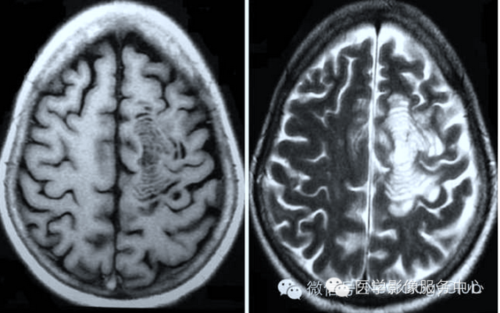

脑白质软化,脑白质脱髓鞘

图文详解脱髓鞘脑病影像诊断

脑白质病变的影像学鉴别诊断